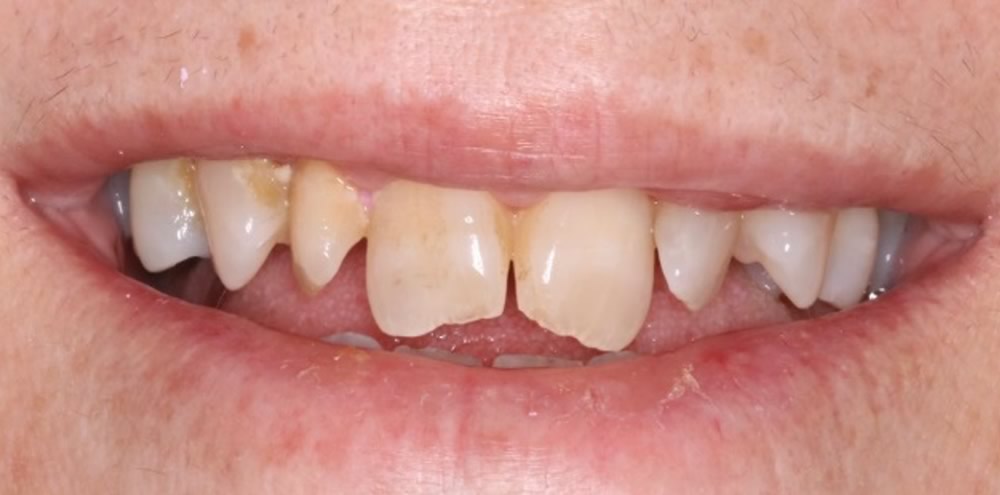

A Prótese Dentária é uma especialidade dentro da odontologia que surge como solução em casos onde se faz necessário a reconstrução de dentes parcialmente destruídos até a reposição de 1 ou mais dentes ausentes na arcada dental do indivíduo.

Durante o planejamento, é indispensável que o profissional analise as diversas opções de tratamento que o caso clínico em questão permite realizar, já que tais procedimentos possuem muitas implicações funcionais e estéticas que devem ser trabalhadas criteriosamente para que o resultado seja realmente satisfatório.

Cada planejamento é único e individual, baseado sempre em exame clínico e exames complementares (exames radiográficos, fotografias, tomografia computadorizada, enceramento de diagnóstico, etc.).